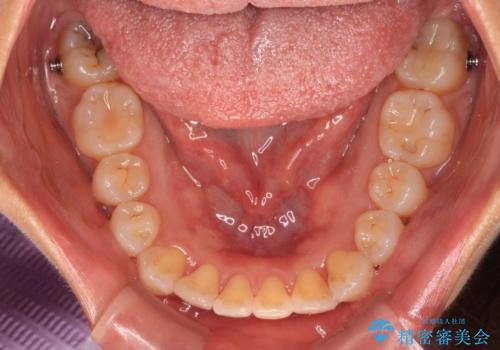

前歯のクロスバイト インビザラインによる矯正治療

- 上下のクロスバイトと前歯のデコボコを気にして来院された患者様です。

インビザラインを用い、IPR(歯と歯の間を削る)と歯列全体を拡大させることで、歯並びを整えていくこととしました。

インビザライン特有の、治療後半に奥歯が咬み合わないという事象が長引きました。

咬み合わないときの対処方法は色々とありますが、ゴムかけなどを活用して噛めるようにしました。